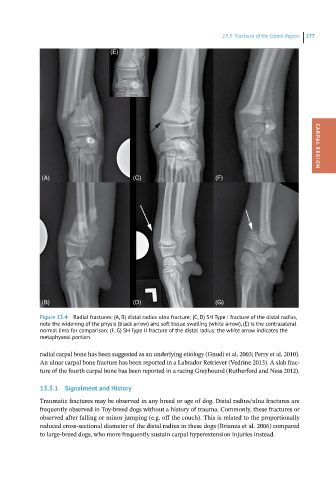

Figure 13.4 Radial fractures: (A, B) distal radius ulna fracture; (C, D) SH Type I fracture of the distal radius,

note the widening of the physis (black arrow) and soft tissue swelling (white arrow), (E) is the contralateral

normal limb for comparison; (F, G) SH Type II fracture of the distal radius: the white arrow indicates the

metaphyseal portion.